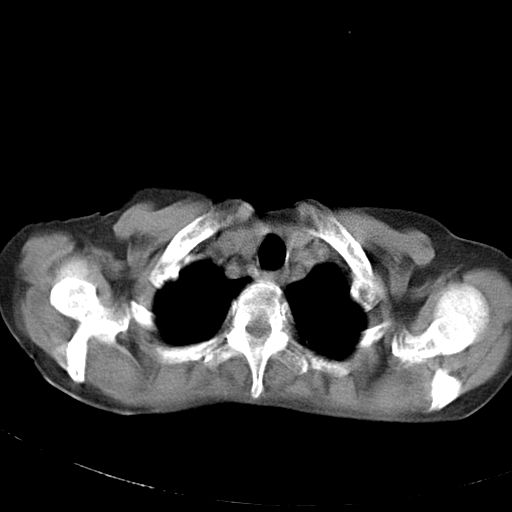

以下是引用dyqct在2006-12-7 21:08:00的发言:[br]考虑:1、肝内外胆管多发性结石伴肝左叶外侧段肝萎缩;[br] 2、右膈下多发脓肿;[br] 3、右侧少量胸腔积液、斜裂积液;[br] 4、左肾囊肿。

以下是引用jiazh在2006-12-7 20:37:00的发言:[br]肝脏周围半狐形低密度影,肝脏表面受压推移,考虑膈下脓肿可能性大;2、右侧胸腔积液

以下是引用拾荒者在2006-12-7 21:44:00的发言:[br]肝内外胆管多发结石,右膈下多发脓肿,右胸膜腔及叶间裂积液,左肾囊肿。[br] [br]